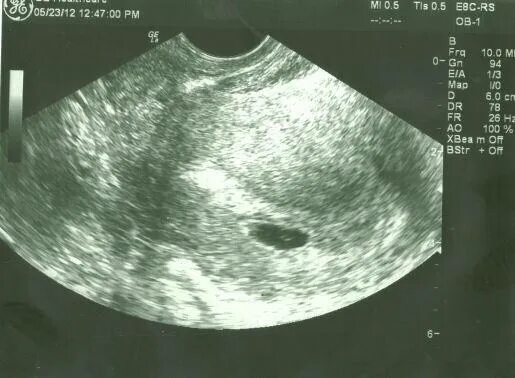

4 неделя берем